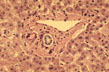

Formations of the Portal Space

Fig 24 - Portal Space

PORTAL ARTERIOLE: Located close to the portal bile duct.Small arterioles may penetrate into the lobule.

PORTAL VEIN: Large,thin -walled perforates the limiting plate and connects with sinusoids.Terminates at the equator of the acinus were it forms the terminal portal vessel,not visible in normal conditions.

PORTAL BILE DUCT: Identifiable for its location close to the portal arteriole.

CHOLANGIOLES: Called also bile ductules and ducts of Hering are situated at the periphery of the portal space.

PORTAL LYMPHATICS: Invisible,are around vessels and bile ducts.They drain lymph from the Disse spaces to the hilus of the liver connecting with lymphtics from the glissonian capsule.

INFLAMMATORY CELLS: Presence of lymphocytes and macrophages is normal.Presence of polymorphs, eosinophils and plasma cells is abnormal.

CONNECTIVE TISSUE: Consists of interlacing type I collagen fibers.There is elastic tissue which increases with age.

PERIPORTAL LIMTING PLATE:It is a row of small hepatocytes immediately around the portal connective tissue.

SPACE OF MALL: Space between limiting plate and portal field.It contains villi .

NERVES: Sympathetic from coeliac ganglion and parasympathetic from vagus.They regulate metabolism and vascular and ductal motility.Adrenergic,cholinergic and peptidergic fibers penetrate the lobules where VIP, glucagone,substance P and calcitonin are identified.